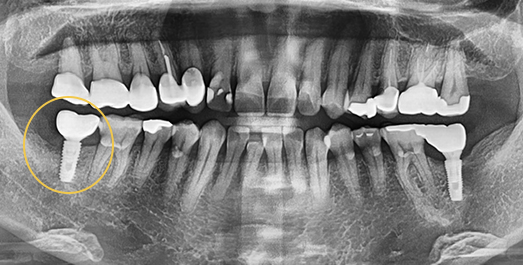

Sinus Lift (Sinus Augmentation)

We build up the bone where needed, even when alveolar bone is insufficient.

The maxillary sinus is an air-filled cavity located on either side of the nose, just above the upper alveolar bone, and is lined by a thin membrane. When placing implants in the upper posterior molar region, insufficient alveolar bone in this area may cause the implant to penetrate into the sinus cavity. To prevent this, a surgical procedure called sinus lift (sinus augmentation) is performed — which involves elevating the thin sinus membrane and grafting bone material into the space beneath it.

• BEFORE: 2021.02.01

• AFTER: 2021.05.13